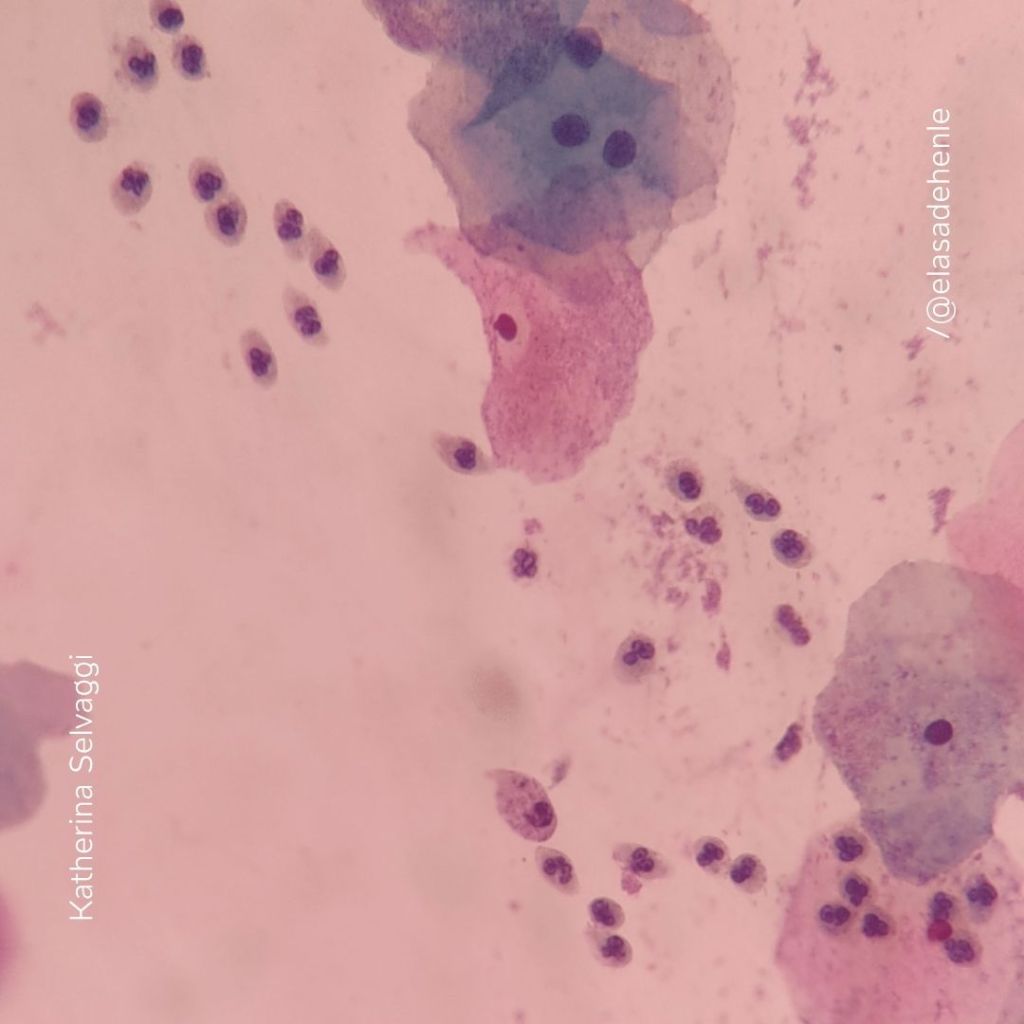

PAP

Citología cérvico – vaginal

Instituto Nacional del Cáncer